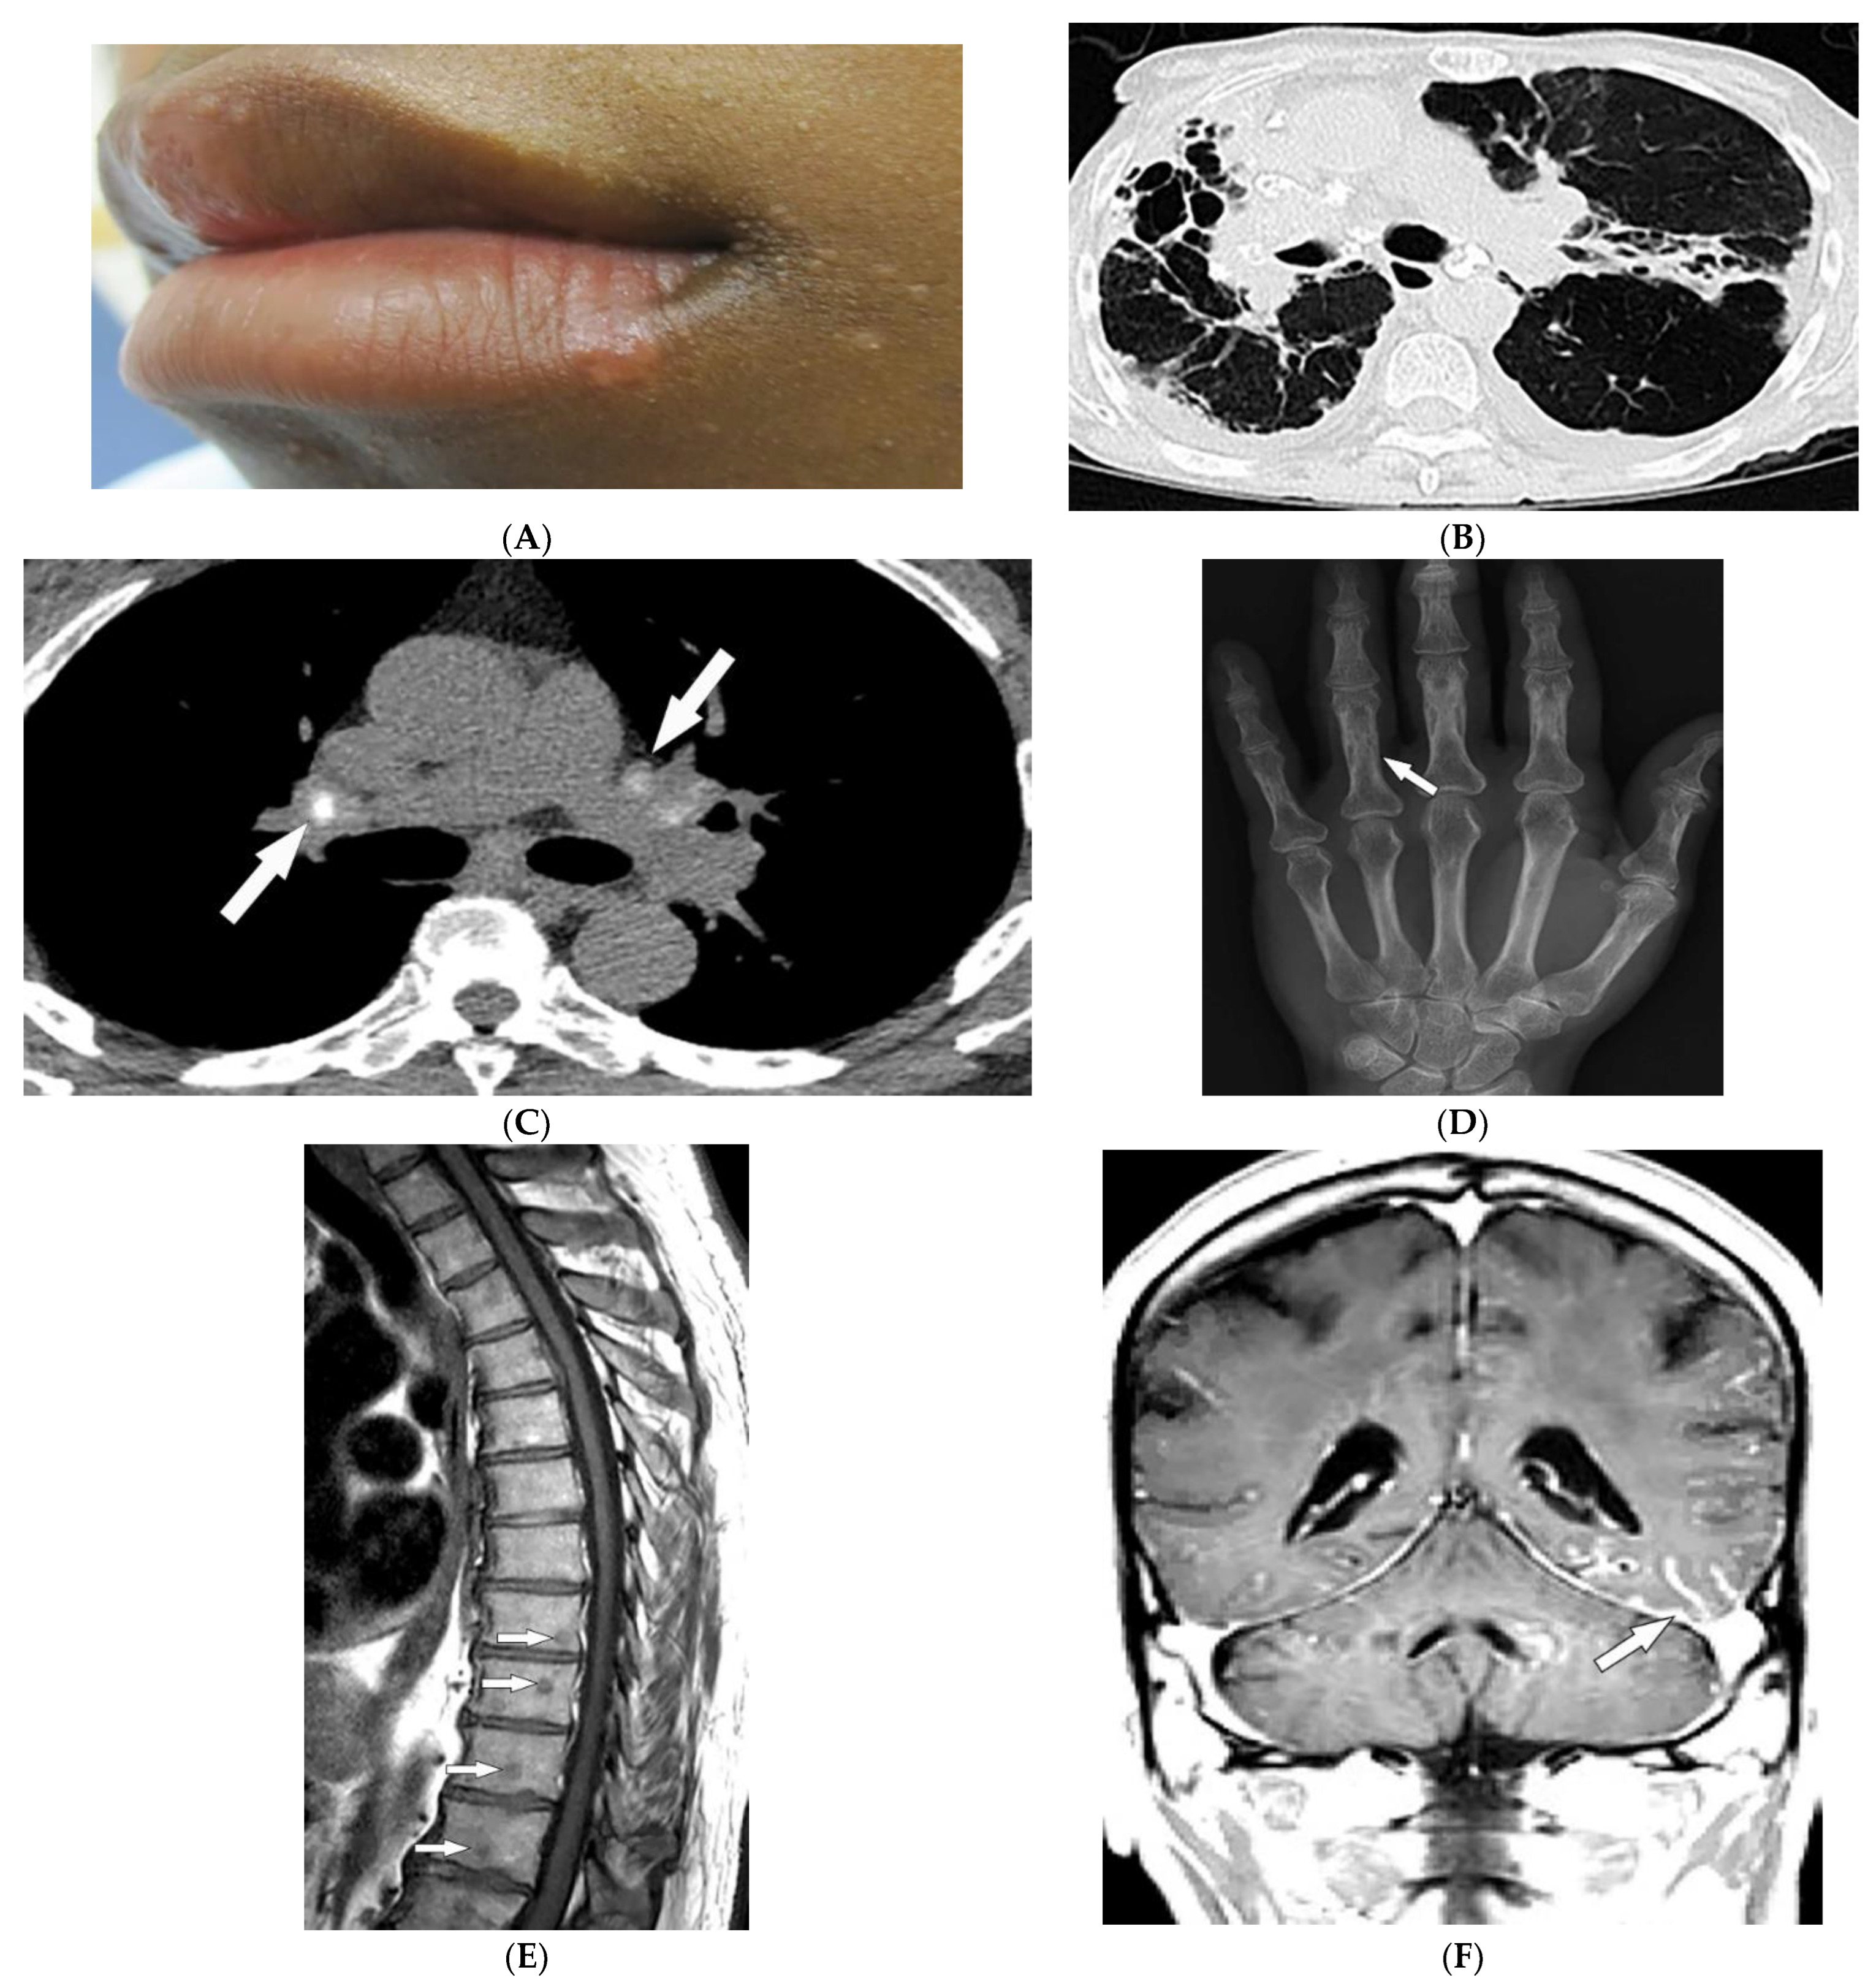

2.2. Sarcoidosis

| Sarcoidosis | Lupus pernio Erythema nodosum Lung nodules and adenopathy neurosarcoidosis Bone lesions | Reticulonodular lung opacities with upper lobe and peri-lymphatic distribution Leptomeningeal enhancement Lacy lytic bone lesions |